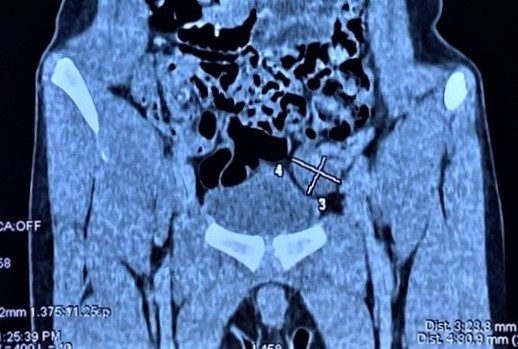

| Tinh hoàn bé trai "chạy" lên ổ bụng. |

Các bác sĩ tiến hành thăm khám, xác định chỉ có tinh hoàn phải ở trong bìu, còn tinh hoàn trái không có ở bìu, và khám không thấy ở ống bẹn trái. Vì vậy tiếp tục siêu âm, chụp cắt lớp vi tính để tìm kiếm chính xác vị trí của tinh hoàn trái. Kết quả cận lâm sàng cho thấy tinh hoàn trái của bé trai…chạy lên ổ bụng.